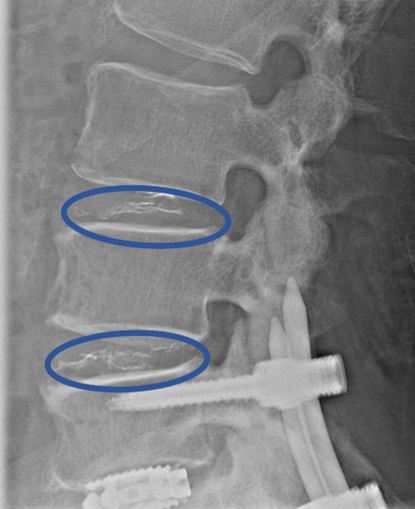

DiscoGelを入れた後の画像になります。

治療は 20分程度で終了

回復室で休憩後、歩いて帰院されました。